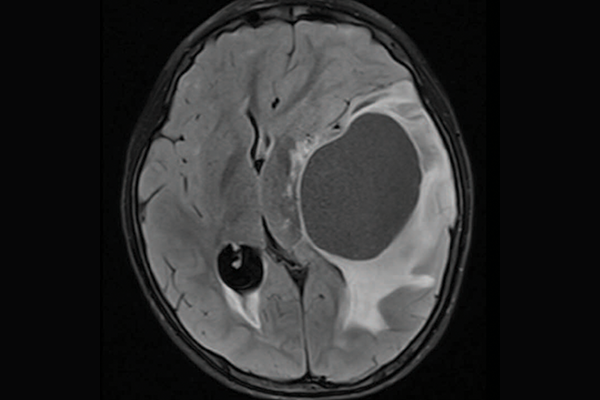

Brain scans showing three different subtypes of priMMRD high-grade glioma.

A scan of a brain with priMMRD subtype 3

priMMRD-3: The immune-cold

Accounting for the remaining 19 per cent of gliomas studied, these tumours have MMRD mutations and a variation in the IDH1 gene. While they often have poor responses to immunotherapy alone, SickKids clinicians and scientists are working toward a clinical trial to pair targeted immunotherapies with a IDH1 inhibitor to provide more tailored care for this subgroup of patients.